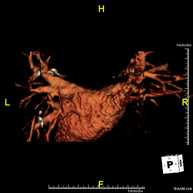

Prueba diagnóstica no invasiva que consiste en la obtención de imágenes de alta definición anatómica de las arterias cerebrales, mediante el empleo de un campo electromagnético y ondas de radio (con un emisor y un receptor). No utiliza radiación ionizante. En la mayoría de los casos es necesario el empleo de contraste paramagnético (Gadolinio). Permite un estudio angiográfico no invasivo gracias a la inyección de Gadolinio con posterior reconstrucción en 2D y 3D, gracias a estaciones de trabajo especializadas. Indicaciones: Malformaciones vasculares, aneurismas de arterias cerebrales, arteriosclerosis. - Angio-RM Troncos supraaórticos

Prueba diagnóstica no invasiva que consiste en la obtención de imágenes de alta definición anatómica de las arterias carótidas y vertebrales a nivel de cuello, mediante el empleo de un campo electromagnético y ondas de radio (con un emisor y un receptor). No utiliza radiación ionizante. En la mayoría de los casos es necesario el empleo de contraste paramagnético (Gadolinio). Permite un estudio angiográfico no invasivo gracias a la inyección de Gadolinio con posterior reconstrucción en 2D y 3D, gracias a estaciones de trabajo especializadas. Indicaciones: Problemas circulatorios cerebrales, síncope.